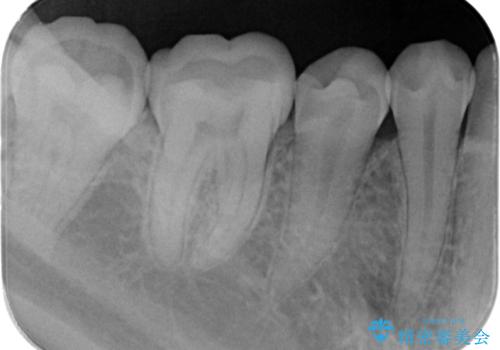

e-maxインレー治療。

- 銀歯を無くしたいとの事で来院。

メタルを除去し、拡大鏡下で虫歯がない事を確認しe-maxインレーで治療を行いました。

適合が良い詰め物が入りました。

セラミックの材料は虫歯の再発のリスクが低くなります。